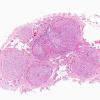

PERIPHERAL NEUROPATHY

9A SARCOID